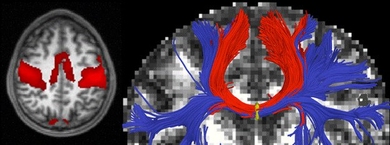

Mapping neurological disease

New algorithm can analyze information from medical images to identify diseased areas of the brain and connections with other regions.